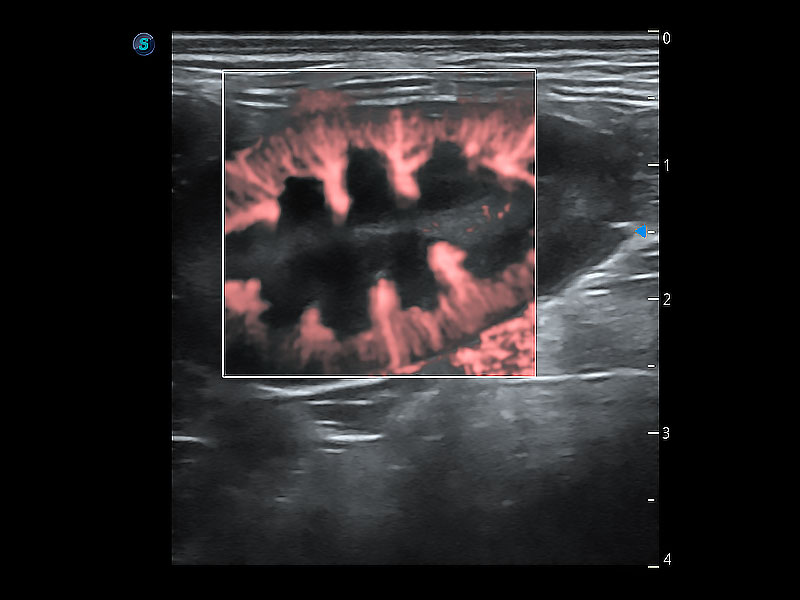

極大提升超低速微細(xì)血流的檢出能力,同時更精準(zhǔn)地濾除軟組織和超聲信號,為獸用醫(yī)生提供以往無法通過常規(guī)血流獲得的疾病診斷信息。

在傳統(tǒng)二維血流成像的基礎(chǔ)上,呈現(xiàn)血流的立體感,具有動感的生命力之美。即便是微小的血管也能輕松應(yīng)對,提高了血流的視覺敏感性。